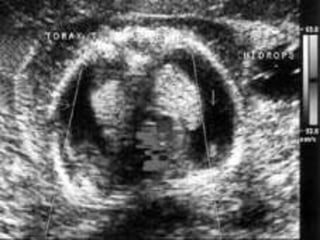

IDIOPÁTICO.

PACIENTE DE 19 AÑOS DE EDAD, III GESTA, II PARA,

FUM: INCIERTA, EMBARAZO ECOGRÁFICO DE 20

SEMANAS + HF.

ESTUDIO CITOGENÉTICO MEDIANTE AMNIOCENTESIS:

CARIOTIPO NORMAL 46 XY.

ECOCARDIOGRAFÍA FETAL NORMAL, VDRL (-), HIV (-).

SE DECIDE CONDUCTA EXPECTANTE, LAS EVALUACIONES

SUCESIVAS NO TUVIERON CAMBIOS.

A LAS 29,3 SEMANAS DESAPARICIÓN DEL HF Y CRECIMIENTO

FETAL EN P50.

A LAS 37 SEMANAS INICIA TRABAJO DE PARTO Y SE OBTIENE

RN NORMAL MASCULINO, PRODUCTO DE PARTO

EUTÓCICO, QUE PESA 2650 G., APGAR 9 PUNTOS.